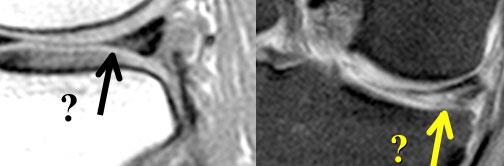

Tăng tín hiệu không chạm rõ ràng đến bề mặt. Đường đen nhỏ ở bờ dưới sụn chêm. Khi nội soi khớp, sụn chêm hoàn toàn bình thường.

Đây là một quan niệm sai lầm khi cho rằng sụn chêm phải đồng nhất giảm tín hiệu trên ảnh mật độ proton (proton-density).

Sụn chêm không nhất thiết phải có màu đen.

Chỉ khi tín hiệu cao chạm rõ ràng đến bề mặt sụn chêm, bạn mới có thể chẩn đoán rách.

Nếu còn nghi ngờ liệu tín hiệu cao có chạm đến bề mặt hay không, hãy xem xét tất cả các lát cắt lân cận.

Nếu vẫn còn nghi ngờ, không nên chẩn đoán rách.

Nếu bạn còn dấu hỏi trong đầu, hãy kết luận “sụn chêm bình thường”. (hình)